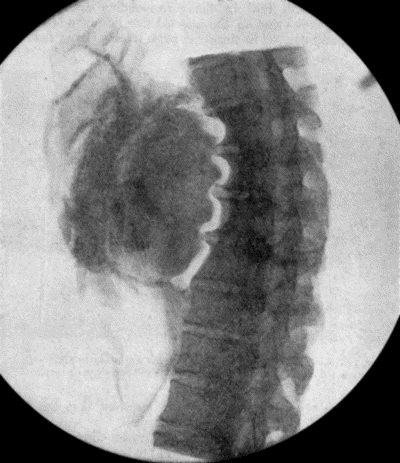

| 71. | Radiogram of Aneurysm of Aorta | 303 |

| 72. | Sacculated Aneurysm of Abdominal Aorta | 304 |

| 73. | Radiogram of Innominate Aneurysm after Treatment by Moore-Corradi method | 309 |

| 74. | Thoracic Aneurysm threatening to rupture | 313 |